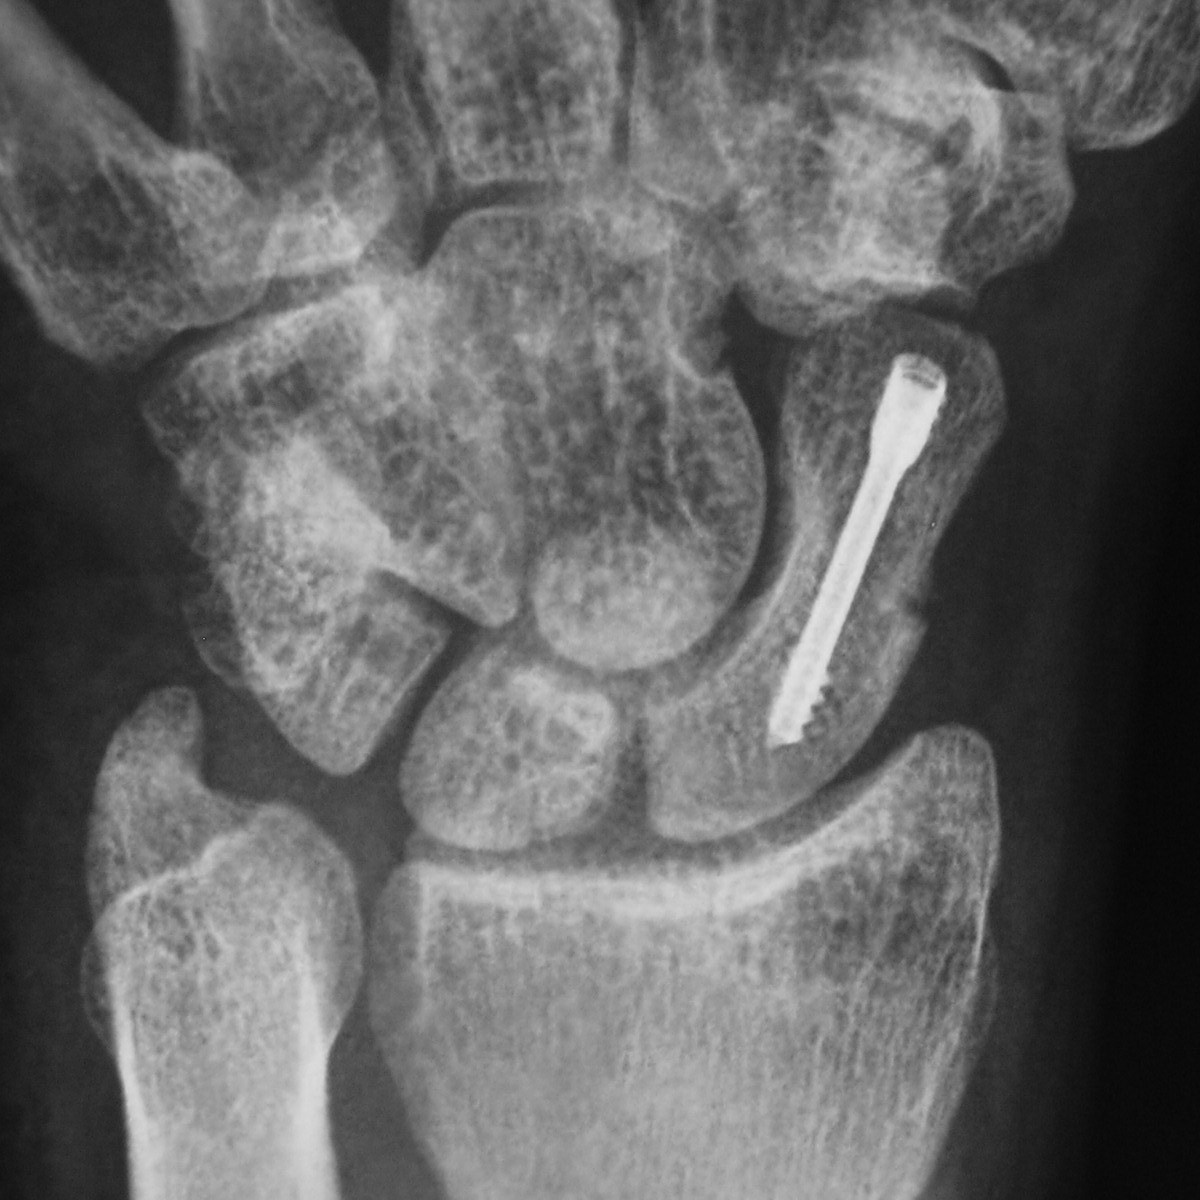

Scaphoideumfraktur

Drabbar ofta yngre individer i samband med sportutövning eller efter annat kraftigt dorsalextensionsvåld. Frakturen är ofta svår att identifiera på slätröntgen varför upprepade undersökningar och/eller CT/MR kan behövas.

Scaphoideum är dåligt vaskulariserad och ofta läker dessa frakturer (ffa proximala polfrakturer) långsamt; 3 månader i gips är normaltid! Gipsen skall immobilisera tumbas, handled och begränsa armens pro-supination. Utebliven läkning (pseudartros) är relativt vanligt och risken ökar om frakturen inte immobiliseras från skadetillfället.

Vid misstanke om scaphoideumfraktur (adekvat trauma, ömhet i fossa Tabatiére)

- Immobilisera i scaphoideumgips även om röntgen bedöms normal.

- Beställ då röntgenkontroll (utan gips) efter 10-14 dagar! Om röntgen är u a även efter 2 veckor, men status kvarstår: ordna snar MR- eller CT-undersökning!

Om skadan missas leder den mycket ofta till pseudartros och senare artros. En smärtsam pseudoartros kräver ofta att man tillför ben från crista illiaca vid operation och vid en handledsartros krävs någon typ av steloperation eller annat större ingrepp.

Det är tyvärr vanligt att frakturen missas då patienten kan uppleva symtomen som en distorsion, men det är också ganska vanligt att det missas av den undersökande doktorn. Detta sammantaget (s.k. 'patient's and doctors’ delay') innebär tyvärr att pseudoartrosoperationer är ganska vanliga.